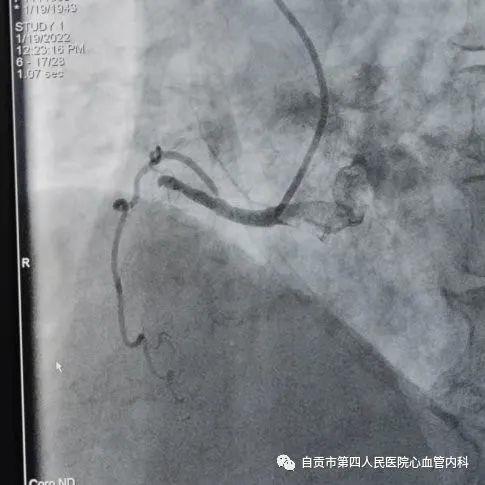

作者:汤勇 自贡市第四人民医院心血管内科引进又一利器“冠脉内超声检查(IVUS)”,助力冠心病精准治疗,目前我国冠心病发病率呈现一个高发的态势,冠心病的发病年龄也呈年轻化的趋势,20-30岁的人群发生急性心肌梗死也不少见。 ![]() 冠脉完全闭塞导致心梗 ![]() 急诊手术成功开通血管 药物加冠脉支架治疗是治疗冠心病的常规治疗手段,我们通常选择冠脉造影对患者的冠状动脉血管检查,由于冠脉造影显示的血管图像是二维图像,并不能完全真实地反映患者冠脉病变的实际情况,有可能造成不必要的支架植入,判断支架的大小完全依赖经验与造影图像,也有可能造成支架大小,长度选择不当。 ![]() ![]() 为了更精准对冠心病患者治疗,优化支架植入,减少支架植入的并发症的发生。 ![]() IVUS图像 ![]() 造影显示需要支架治疗 我院引进了美国波科公司的冠脉内超声检查(IVUS)检查设备,对患者的冠状动脉进行实时检查,为临床医生在对冠心病患者是否需要支架治疗,支架合理应用提供更为准确得信息。 ![]() 我们有一位患者在西昌某院因心肌梗死,行右冠状动脉支架治疗,当时冠脉造影检查提示右冠状动脉支架有一重度狭窄,建议择期再行支架治疗,患者慕名来我院来进一步检查。从冠脉造影的情况确实需要进行支架治疗,由于患者年轻,已安置支架4枚,故决定对患者进行冠脉内超声检查(IVUS)检查。 ![]() 支架局部膨胀不全 ![]() 冠脉内超声检查(IVUS) ![]() 支架直径恢复正常 患者冠脉内超声结果提示管腔面积能够满足心肌血供,且病变邻近血管直径大于5mm,不适合支架治疗。故建议其药物治疗,必要时复查造影。另外该患者造影显示已安置的支架显示膨胀不全的可能,进行冠脉内超声检查后显示支架内有明显膨胀不全的征象,故予以球囊扩张,支架管腔直径恢复正常。 在今后的冠心病治疗上,冠脉超声检查将发挥更大的作用,特别是复杂病变,左主干病变,钙化病变,闭塞病变方面,将大大减少冠脉介入治疗的并发症,再次支架治疗的发生率降低,将大大提高我院冠心病的精准治疗水平。 ![]() ![]() |